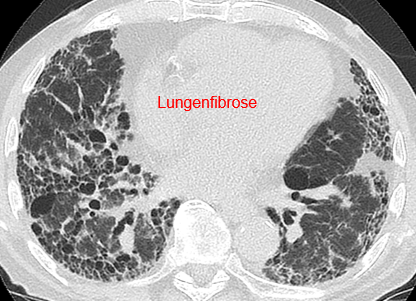

Beispielhafte Aufnahmen verschiedener Erkrankungen

(Lungenklinik Lostau)

Die High-Resolution-Computertomographie (HRCT) ist eine spezielle CT-Technik mit sehr hoher Detailauflösung. Sie ist besonders wichtig für die Diagnostik und Verlaufskontrolle interstitieller Lungenerkrankungen (ILD), da feine Muster im Lungengewebe differenziert beurteilbar werden.

Interstitielle Lungenerkrankungen (ILD) sind Erkrankungen, bei denen sich das Lungengewebe durch Entzündung oder Vernarbung verändert. Die High-Resolution-Computertomographie (HRCT) ist dabei ein zentrales Werkzeug, weil typische Muster in der Bildgebung wichtige Hinweise auf Ursache und Stadium geben.